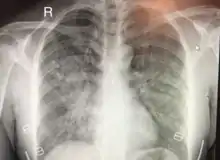

| Chest x-ray of HAPE showing characteristic patchy alveolar infiltrates with right middle lobe predominance. | |

Hypoxic pulmonary vasoconstriction (HPV) occurs diffusely, leading to arterial vasoconstriction in all areas of the lung. This is evidenced by the appearance of "diffuse," "fluffy," and "patchy" infiltrates described on imaging studies of climbers with known HAPE.[8]

On physical exam, increased breathing rates, increased heart rates, and a low-grade fever 38.5o C (101.3o F) are common.[8][3] Listening to the lungs may reveal crackles in one or both lungs, often starting in the right middle lobe.[8][3] Imaging studies such as X-ray and CT imaging of the chest may reveal thoracic infiltrates that can be seen as opaque patches.[13][8][3] One distinct feature of HAPE is that pulse oximetry saturation levels (SpO2) are often decreased from what would be expected for the altitude. People typically do not appear as ill as SpO2 and chest X-ray films would suggest.[8][3] Giving extra oxygen rapidly improves symptoms and SpO2 values; in the setting of infiltrative changes on chest X-ray, this is nearly pathognomonic for HAPE.[3]